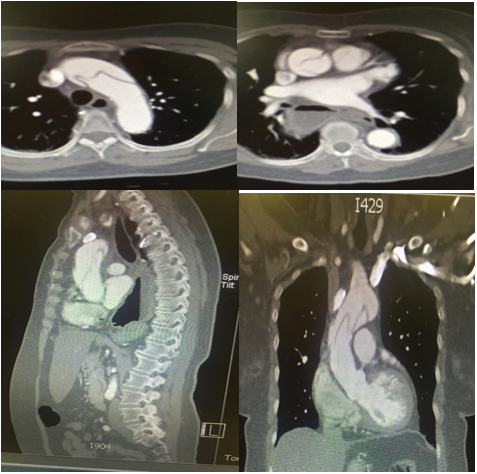

A 80-year-old female patient with past medical history of arterial hypertension, hypothyroidism, chronic lung disease, hiatal hernia, and moderate aortic stenosis was admitted to the emergency department for one hour of evolution of pain in the submandibular region and the right arm, with loss of strength in this limb, without dyspnea or chest pain. Physical examination revealed hypotension, without altered consciousness or tachycardia, right arm with decreased force, coldness, weak radial pulse, and prolonged capillary refill, adequate femoral pulses, and normal cardiopulmonary auscultation. Acute aortic pathology was suspected; chest X-rays showed mediastinal widening; due to the high probability and clinical suspicion of an acute aortic syndrome (AAS), an angio-CT scan was requested, showing type-A aortic dissection with involvement of the right subclavian artery (thrombosis) and the brachiocephalic trunk. The patient was referred to another institution for assessment by cardiovascular surgery, who analyzed the case and due to the patient’s comorbidities, age, and extension of the vascular affection; non-surgical expectant management was decided. She remained in ICU for 24 hours. The next day, the patient presented a convulsive episode, followed by cardiorespiratory arrest. No CPR maneuvers were performed due to previous dissent; the patient died (Figure 1).

Figure 1 Angio-CT scan: Type- A aortic dissection that extends to the right brachiocephalic trunk. Thrombosis of the right subclavian artery. Evidence of atherosclerosis, hiatal hernia, simple hepatic cysts, fatty liver, right renal cyst with calcified walls, and simple cyst in the left kidney